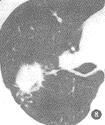

2、CT檢查

CT圖像把假瘤與肺的境界面顯示得非常清楚,即使胸片表現為大片狀或團塊狀模糊影,但在CT圖像上則表現為境界清楚的塊影。CT掃描比胸部平片更容易發現小空洞的存在,這種小空洞可以單發,也可以多發。除此以外,CT圖像上顯示腫塊周圍長毛刺胸膜增厚粘連征像對本病診斷有著重要意義。

2.2 大小與密度 腫塊直徑1.5~8cm之間,其中≤3cm4例,≥6cm5例。密度不均勻或不均勻強化6例,平掃CT值25~45Hu,增強掃描CT值45~86Hu。病灶內有散在斑片狀鈣化1例。

2.3.2 腫塊型 形態不規則3例,類圓形邊緣光滑6例。其中分葉2例;有粗毛刺4例;腫塊周圍有薄片狀、格線狀改變5例;平直征2例;桃尖征2例;內側緣引流支氣管影4例;腫塊內小空泡或支氣管影3例;胸膜增厚、粘連3例。所有病例CT檢查均未見縱隔淋巴結腫大。

腫塊近肺門側引流支氣管影、周邊暈圈樣改變和格線狀改變及無肺門和縱隔淋巴結腫大等都有助於與肺癌鑑別。CT隨訪複查有助於病灶的動態觀察,提高診斷的準確性,但仍需結合其他各種檢查綜合分析以避免誤診。

肺炎性假瘤X線表現:假瘤可發生在肺的任何部位,球型瘤體由於有較完整的假性包膜,因此輪廓清楚,邊緣光滑,周圍肺野清晰。團塊狀的瘤體由於假包膜不完整,一般境界不清,邊緣模糊,部分病灶密度濃淡不勻,如多次並發急性炎症,可造成“瘤”影擴大,在其周圍恰似炎性浸潤的片狀影。崔氏報導的“桃尖征”本組出現率不高,其病理基礎可能是一種腫瘤包膜粘連的徵象;CT表觀:CT圖像把假瘤與肺的界面,特別是假瘤的邊緣、密度、空洞、長毛刺影與胸膜粘連等顯示得非常清楚。本文36例胸部平片僅2例見有空洞影,而25例CT掃描發現9例小空洞,這種空洞可以單發也可多發。少數瘤體切開時可見膿性物。假瘤邊緣可以不規則或呈鋸齒樣,也可呈分葉狀。CT肺窗圖像上,腫瘤邊緣可清楚地顯示炎性滲出影。長毛刺、與胸膜緊貼或有粘連帶等對本病的診斷具有一定的意義。假瘤術前診斷的主要方法靠X線、CT檢查。胸部正側位相能顯示假瘤的全貌,CT掃描有助於顯示瘤體內部結構(即空洞、鈣化、毛刺、血管、纖維索條影等)。